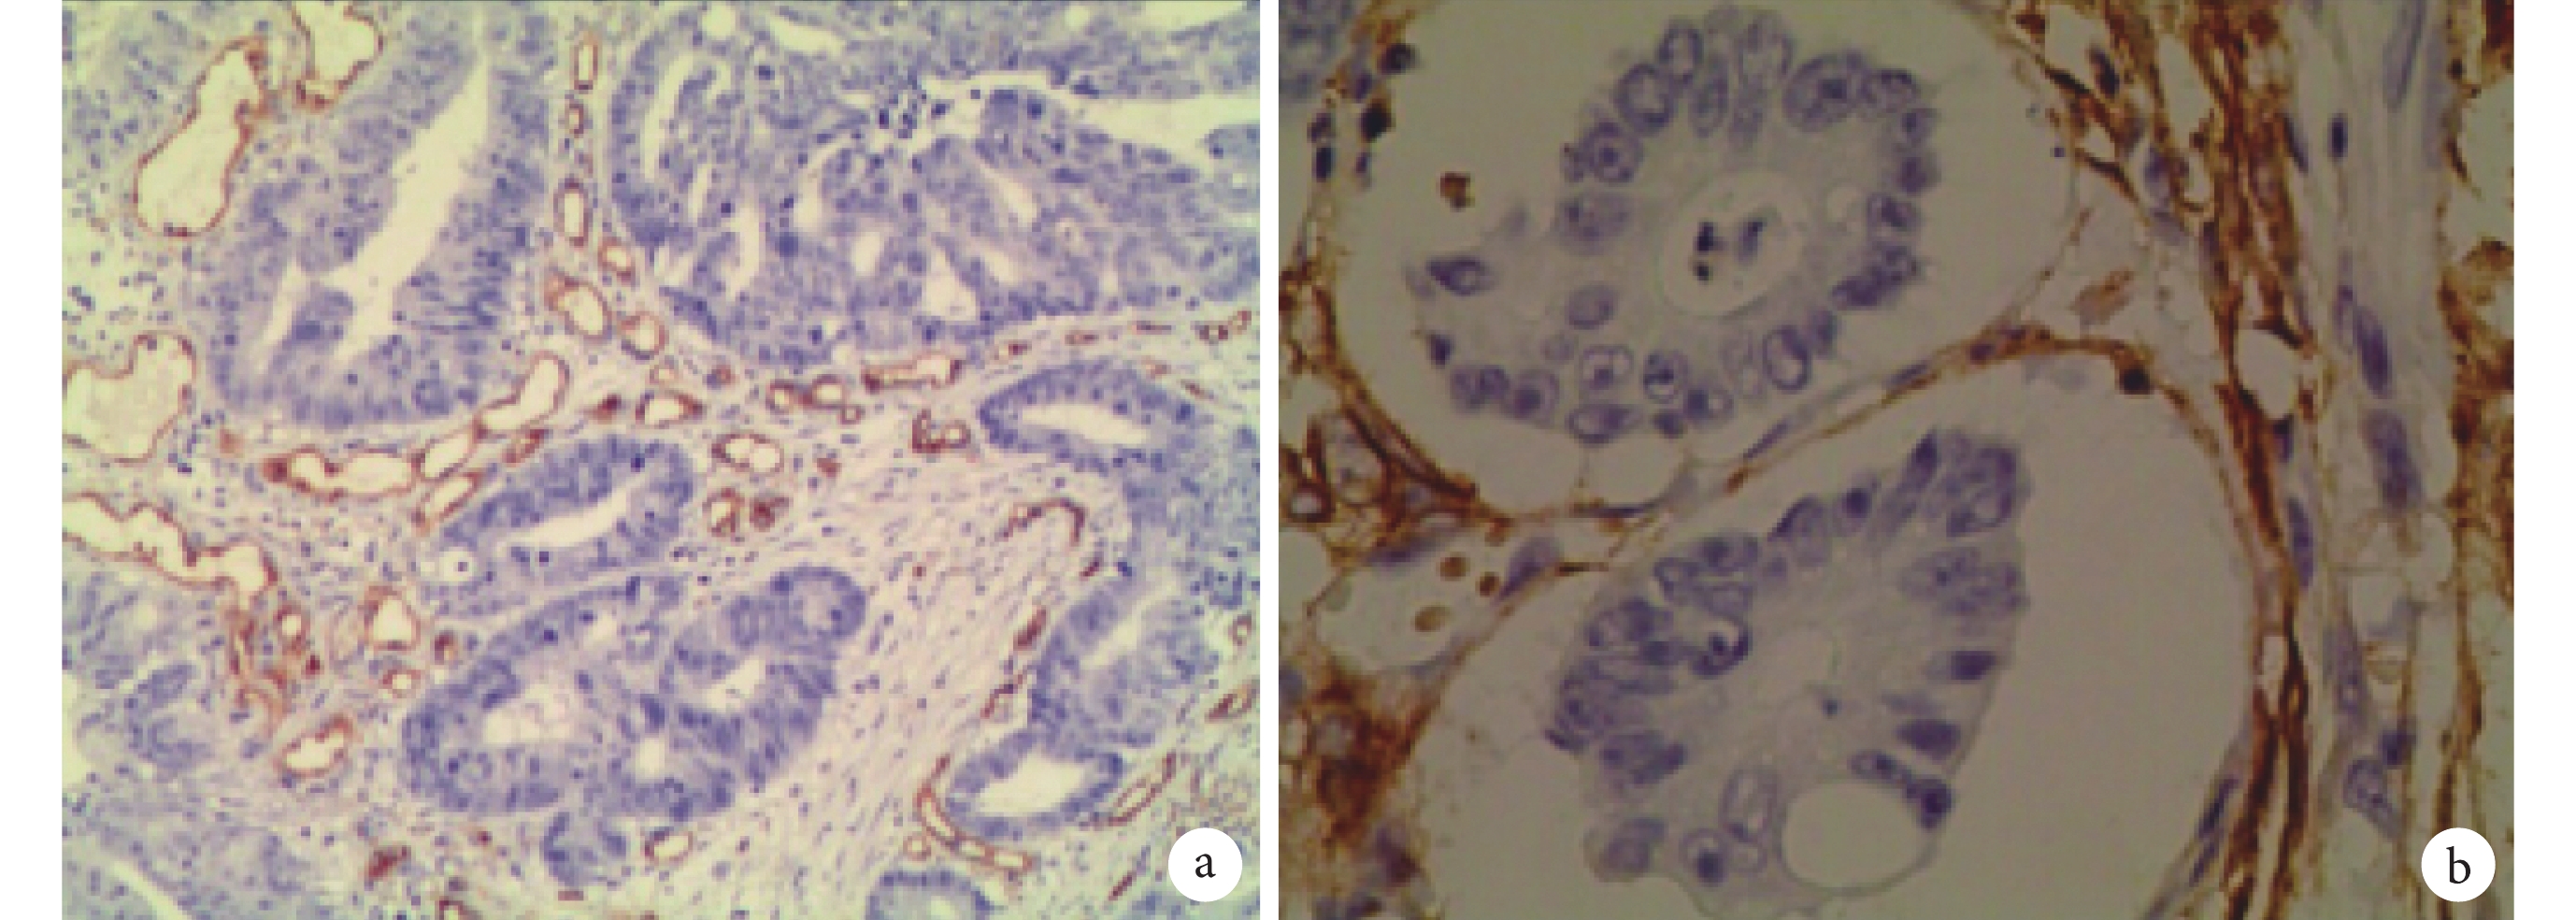

免疫組織化學方法檢測 CD31 及 D2-40 蛋白表達結果見圖 1–3。